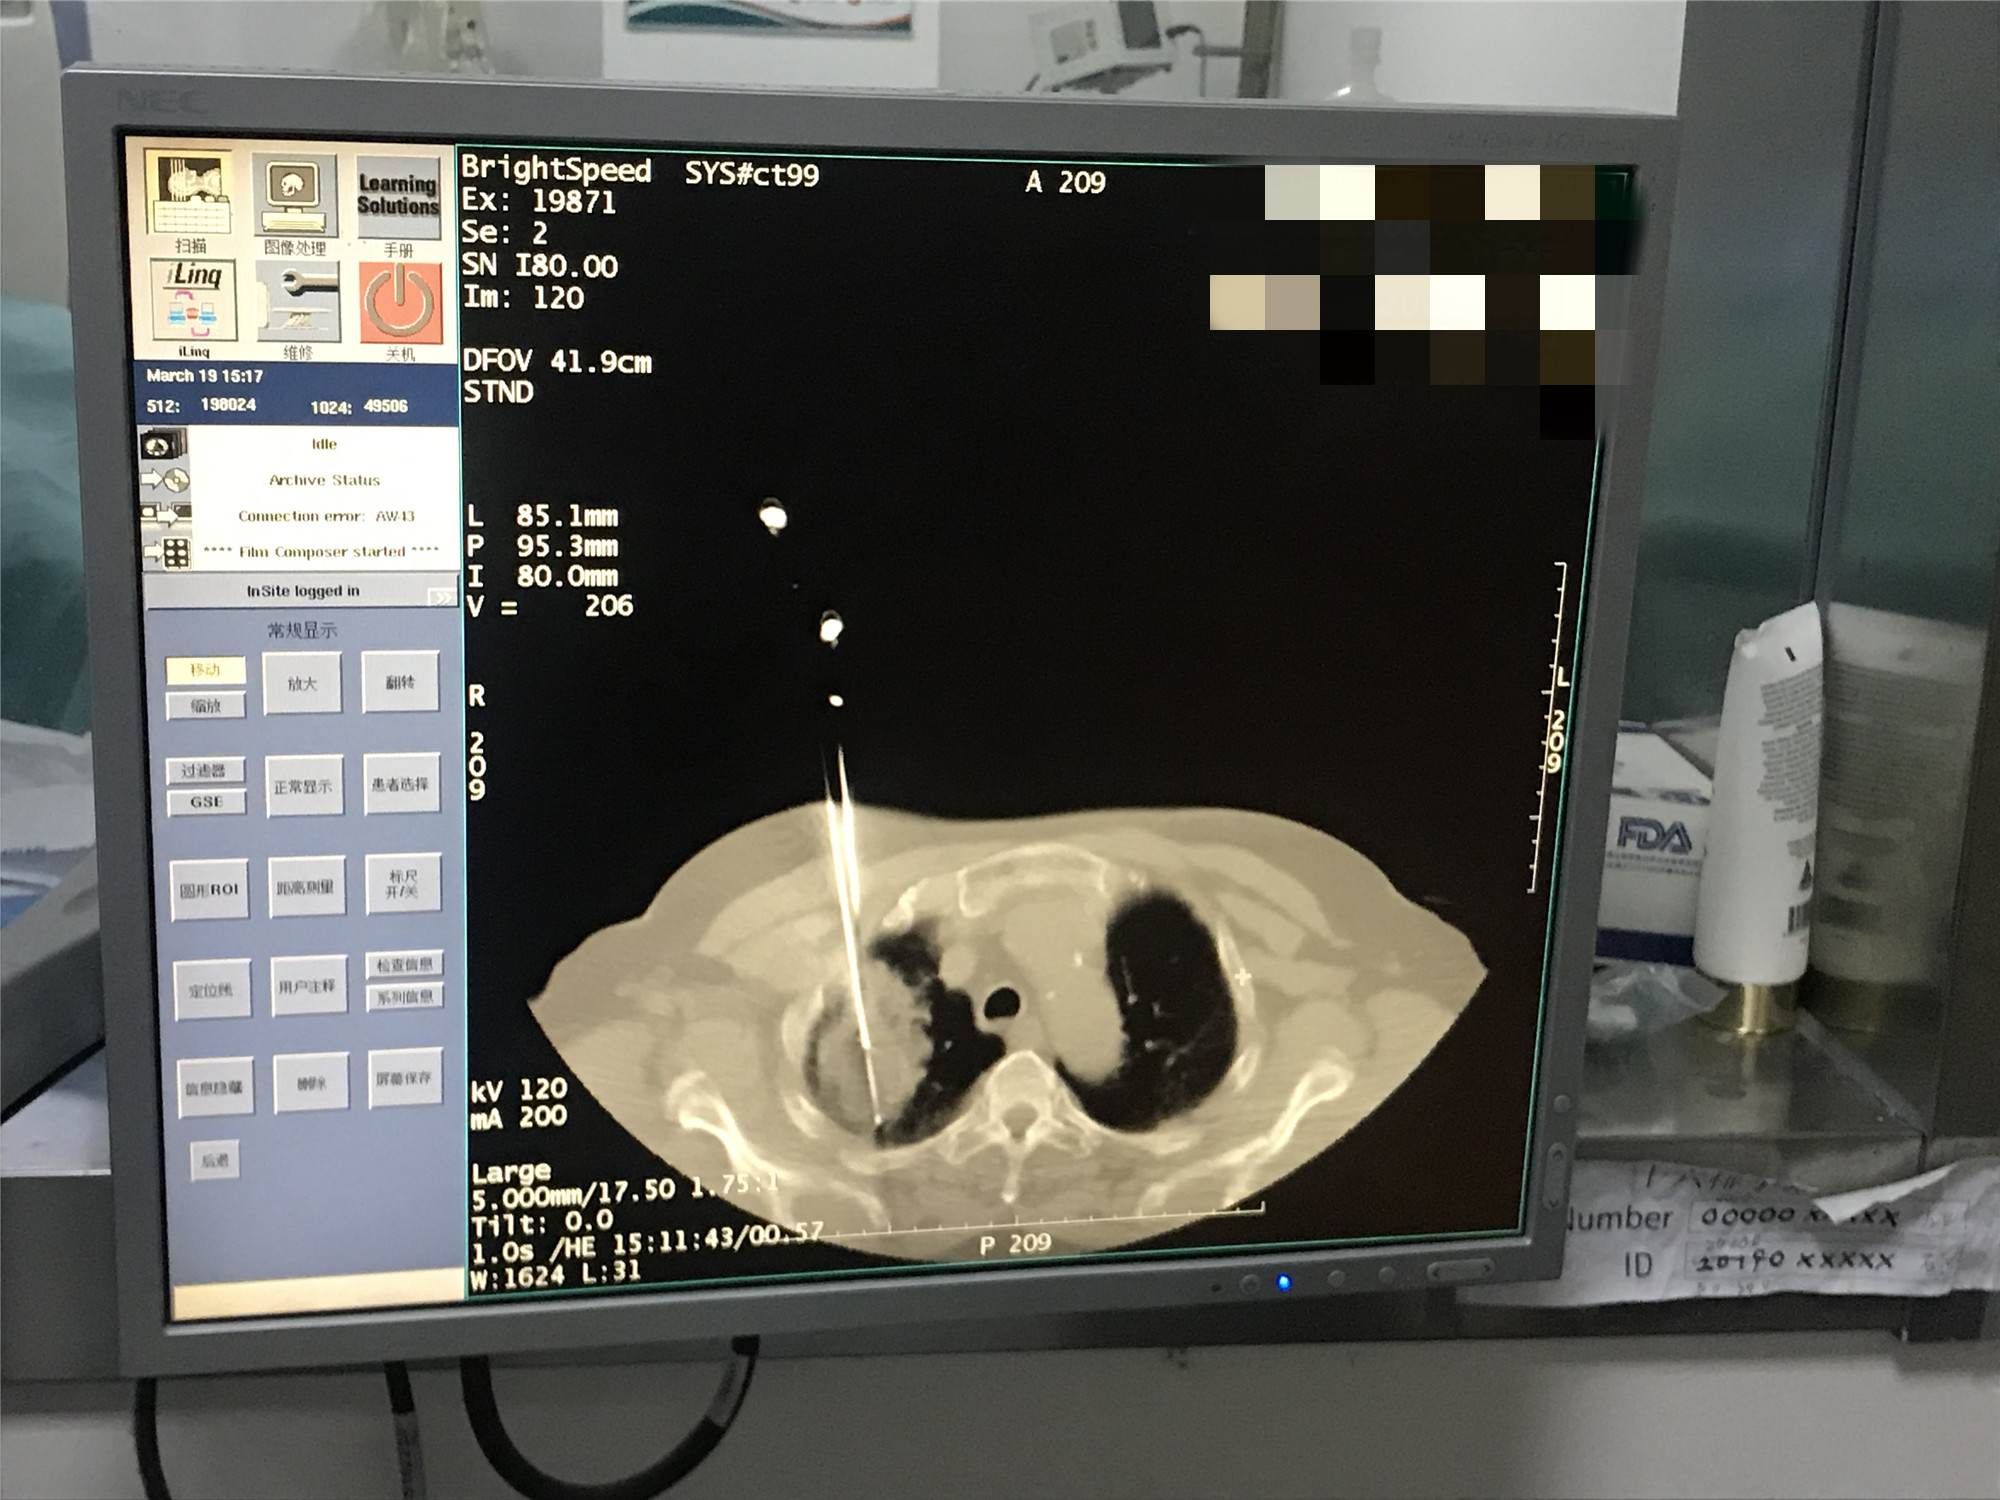

2021年3月份肺部氩氦刀手术